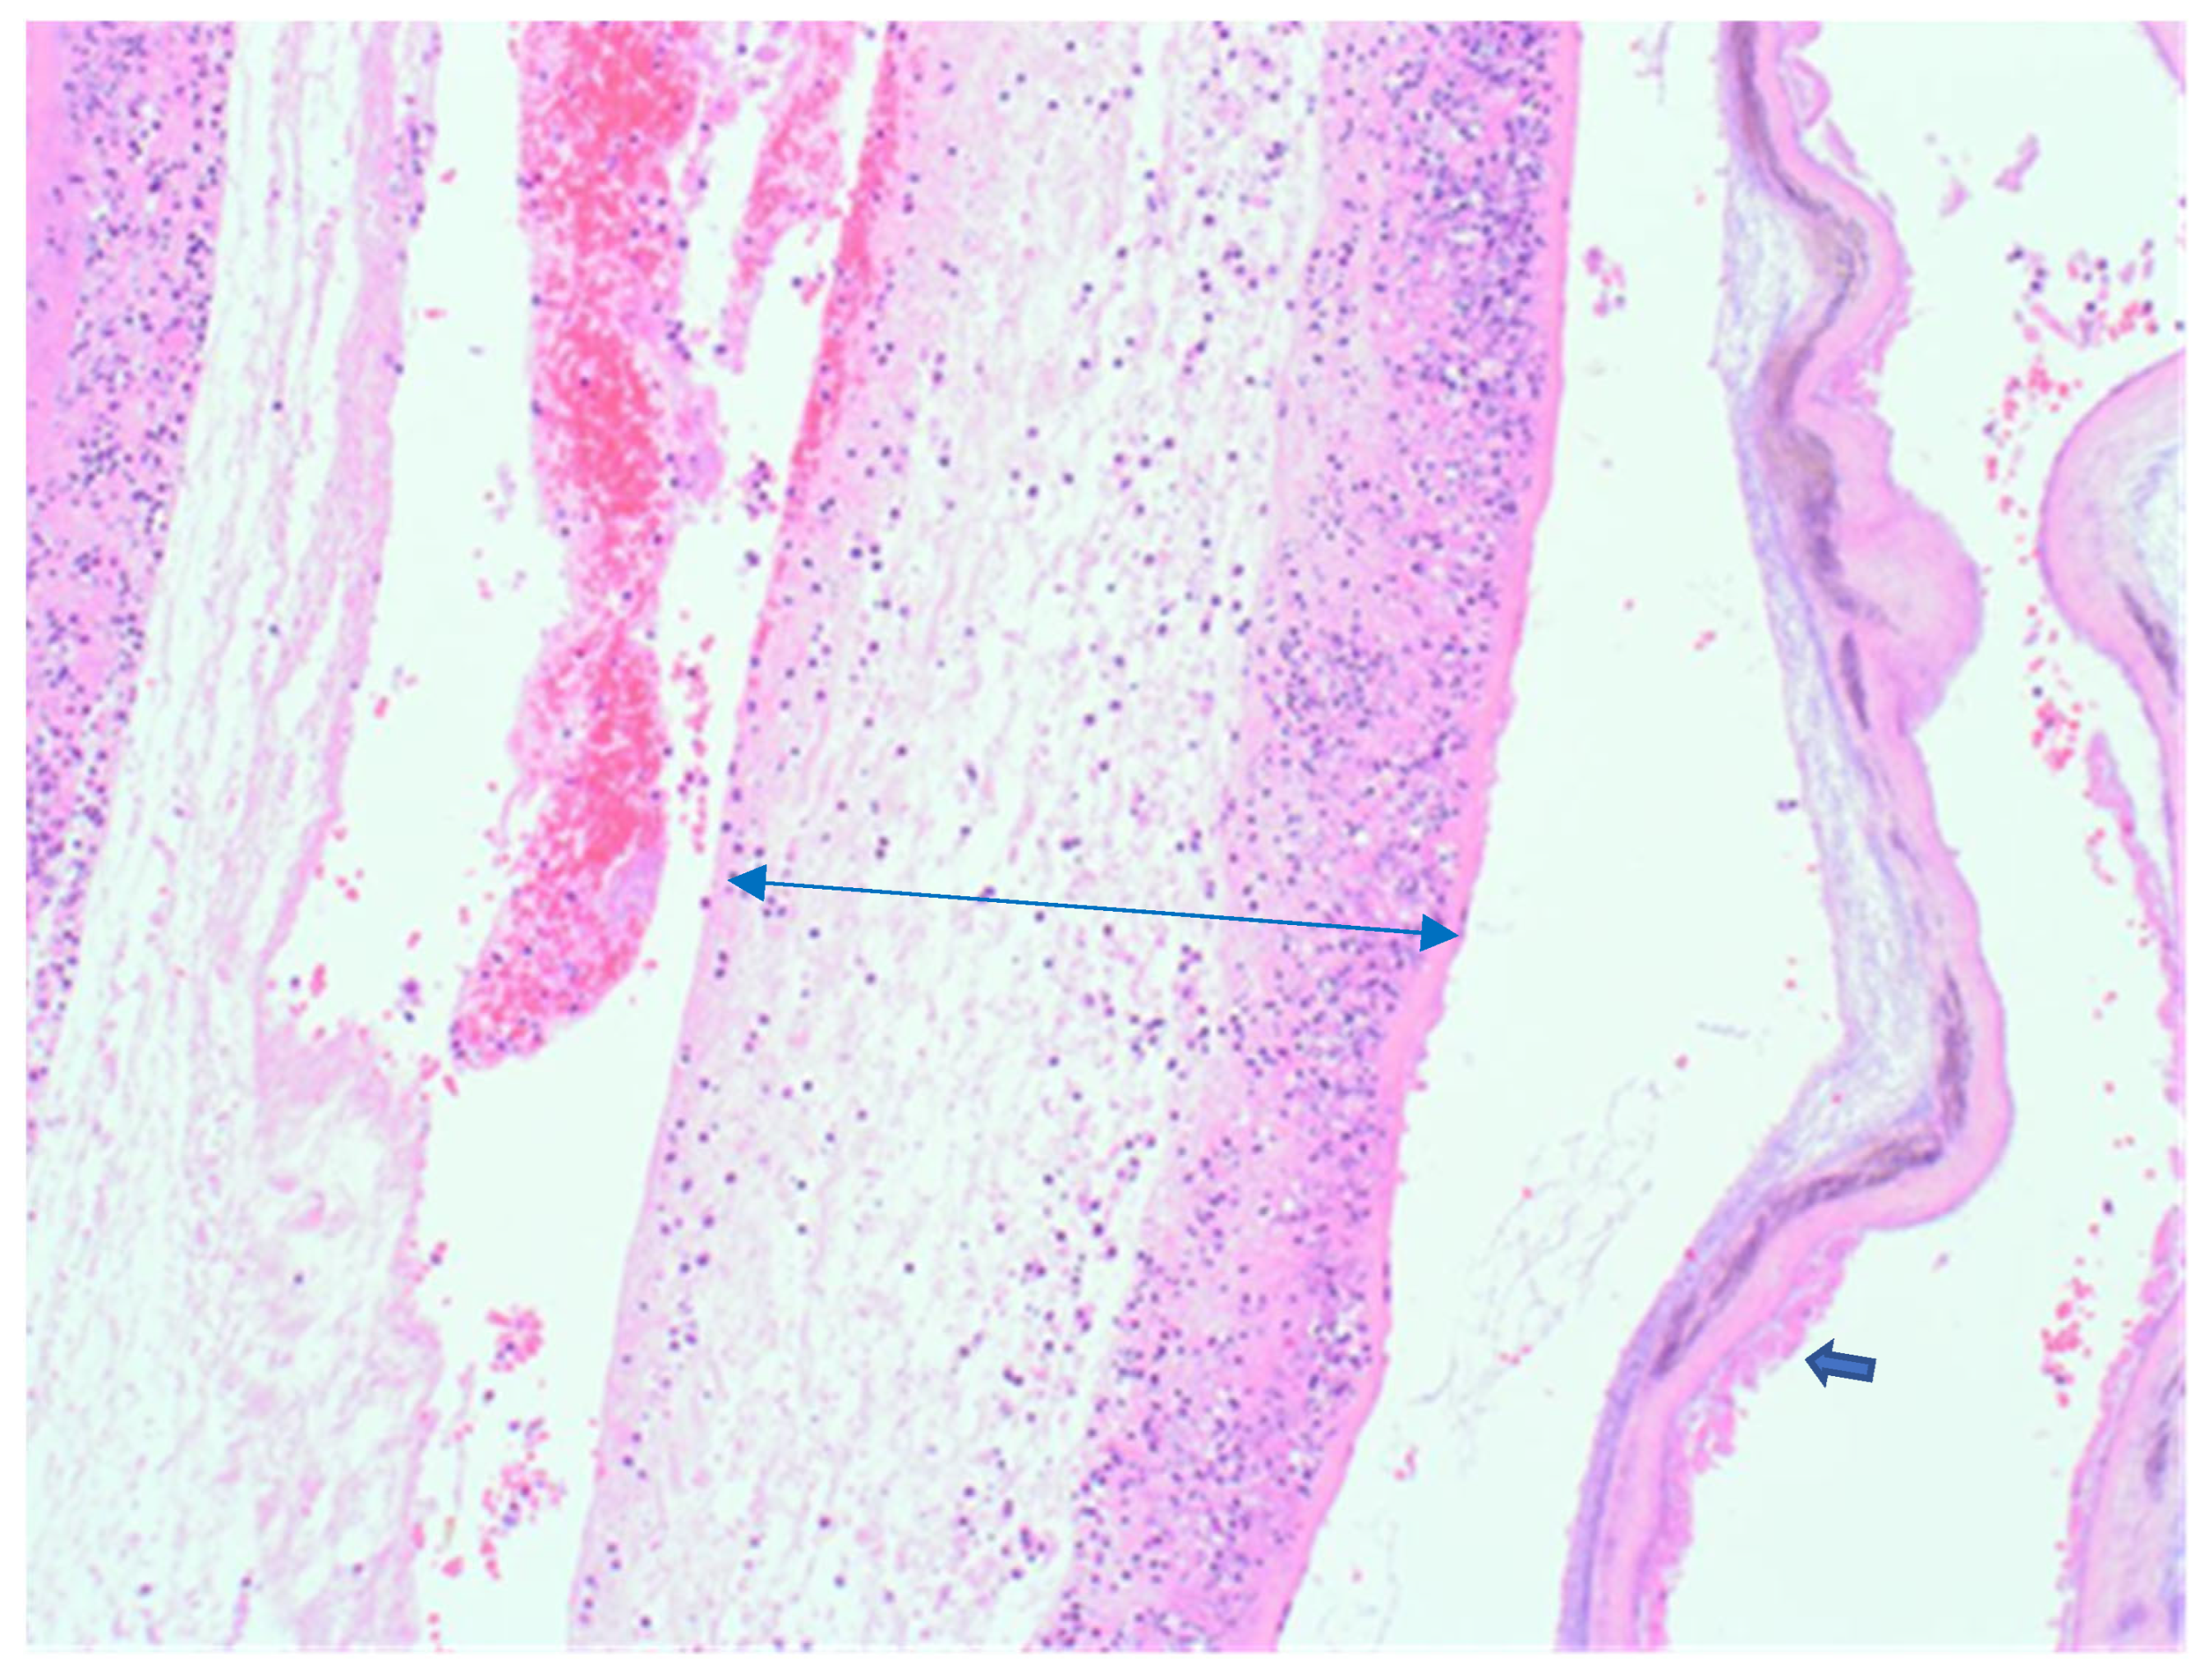

The sample received in the histopathology department was a disc of placenta and membranes with an eccentrically inserted umbilical cord. The placenta trimmed of the membranes weighed 145 mg. The membrane appeared complete and was mostly translucent but with patchy areas of opacity. Microscopy revealed patchy severe acute chorioamnionitis and prominent clusters of Gram-positive filamentous bacteria, which were noted on the surface of the membranes in routine haematoxylin and eosin (H&E) (Figure 1) as well as with Periodic Acid Schiff (PAS) staining (Figure 2). Aggregates of the Splendore–Hoeppli reaction, which are sulphur granules formed from masses of gram-positive bacteria with branching filaments, are also identifiable in Figure 2. The infective organism was revealed to be gram-positive (Figure 3). In this specific case, the microscopic examination indicated the presence of acute inflammation due to an uncommon organism—Actinomyces spp. infection. Sections of the umbilical cord revealed acute inflammation (funisitis), but no organisms were seen in the umbilical cord (Figure 4). During the follow-up visit, the mother did not demonstrate any symptom or sign of infection, her recovery was uneventful, and she remained well during the subsequent reviews.

Figure 1.

Haematoxylin & Eosin (100×). Membranes showing transmural acute inflammation (chorioamnionitis)—double headed blue arrow, with clusters of Actinomyces colonies on the surface of a strip of membrane right (thick blue arrow).